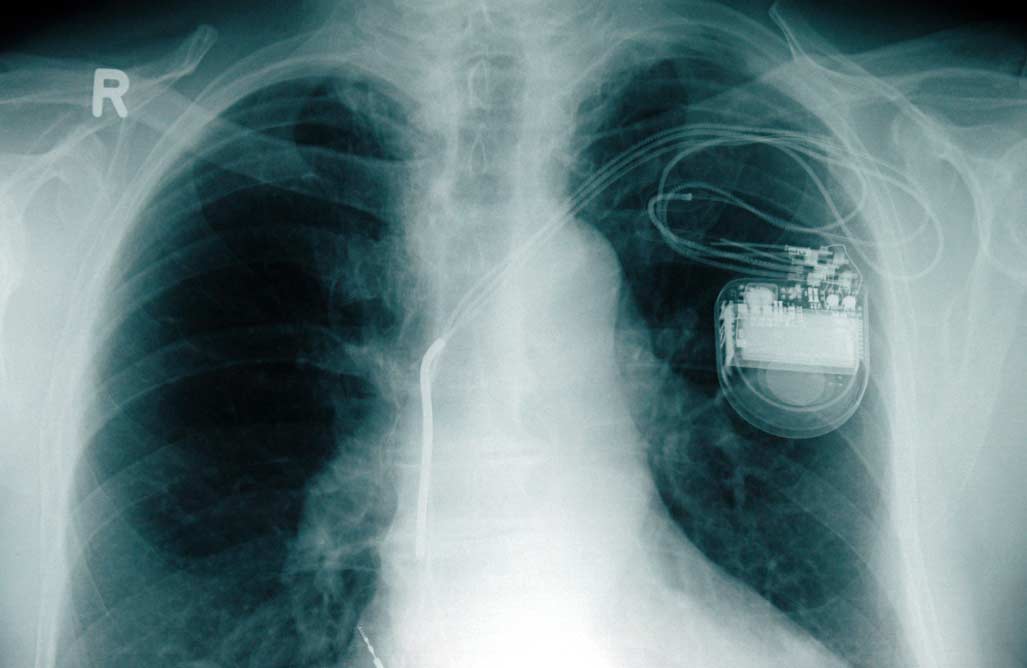

¿Qué descubrieron Lacour, Blaschke y sus colegas? En resumen, el estudio demostró que los iPhone 12 y 13 equipados con anillos magnéticos (tecnología MagSafe) pueden influir en el funcionamiento de los marcapasos y desfibriladores, pero solo en caso de un contacto muy estrecho y tampoco con todos los implantes.

Esto es también lo que sostienen Lacour y Blaschke. En su estudio publicado en noviembre de 2021, ambos académicos probaron todos los implantes cardíacos disponibles en el mercado con la intensidad del campo magnético que emiten constantemente los iPhone con tecnología MagSafe. Para ello realizaron pruebas de laboratorio en las que comprobaron la reacción de los implantes en estrecho contacto con el iPhone 12.

Durante los ensayos se produjeron interferencias en aproximadamente la mitad de los implantes cardíacos. E incluso entonces, estas interferencias solo se constataron a distancias muy pequeñas entre el anillo magnético y el implante: «Por regla general, un máximo de un centímetro», asevera Lacour.

En el caso de los marcapasos, la frecuencia aumenta, informa Philipp Lacour. Con un desfibrilador, se desactiva temporalmente la función necesaria para detener las arritmias cardíacas peligrosas. Una vez que el campo magnético desaparece, el aparato se enciende de nuevo automáticamente.